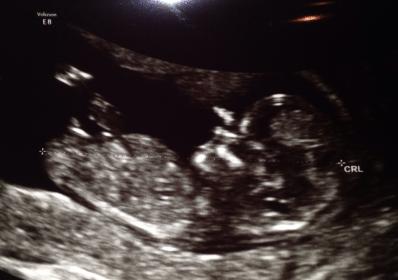

15w2d - gender potty shot

Attachment 7617